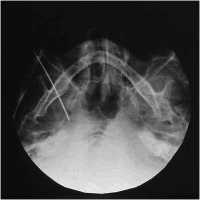

Elektrodenspitze - Foramen ovale

Abbildung 5: Die submentovertikale Röntgenaufnahme der Schädelbasis zeigt die Elektrodenspitze im Foramen ovale rechts.

Keywords: ElektrodeForamen ovaleNeurochirurgieRöntgen